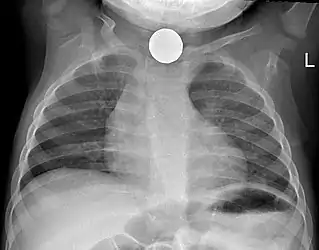

Foreign body aspiration

Foreign body aspiration is a major cause death in young children due their underdeveloped swallowing coordination. Young children most commonly ingest toys, coins, or food.[21] On chest x-ray, the most frequent sign is air trapping that can lead to a mediastinal shift. Atelectasis and pneumothorax may also occur in the setting of foreign body aspiration. The diagnosis is made in conjunction with clinical symptoms and confirmed and treated with bronchoscopy. [22]